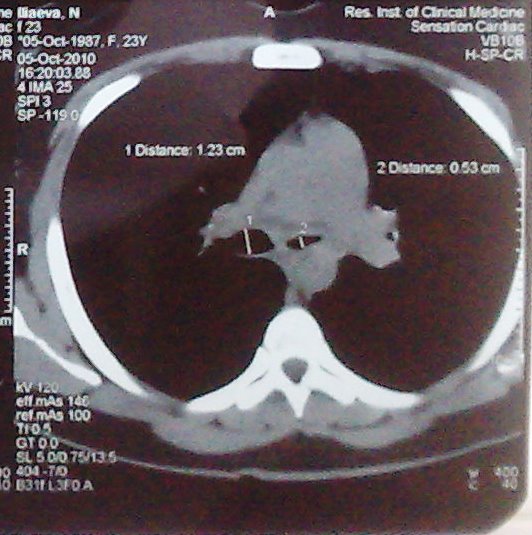

- გულმკერდის კტ სტენტირებამდე (Axial) 8 თვით ადრე

მარჯვენა მთავარი ბრონქის დიამეტრია 12.3 მმ, მარცხენა მთავარი ბრონქის დიამეტრია 5,3 მმ

მარცხენა მთავარი ბრონქის სანათურის დიამეტრია 2.2 მმ